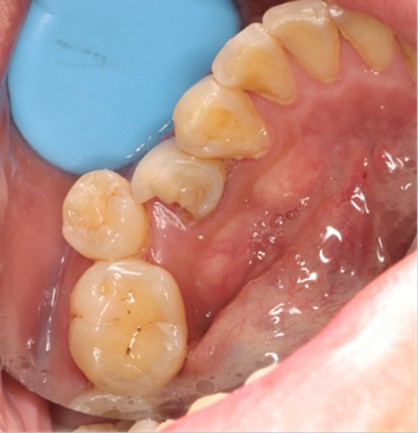

Preoperative Images

May 4, 2025: Extraction of the affected tooth.

Immediate implant placement (first-stage surgery) was performed right after tooth extraction.